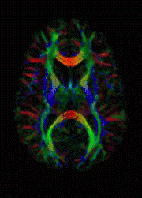

Une représentation similaire associe à chaque pixel une couleur qui dépend de la direction de plus grande diffusivité locale, selon un code prédéterminé. Sur l'exemple ci-contre, le rouge représente l'axe gauche-droite, le bleu l'axe cranio-caudal et le vert, l'axe antéro-postérieur.